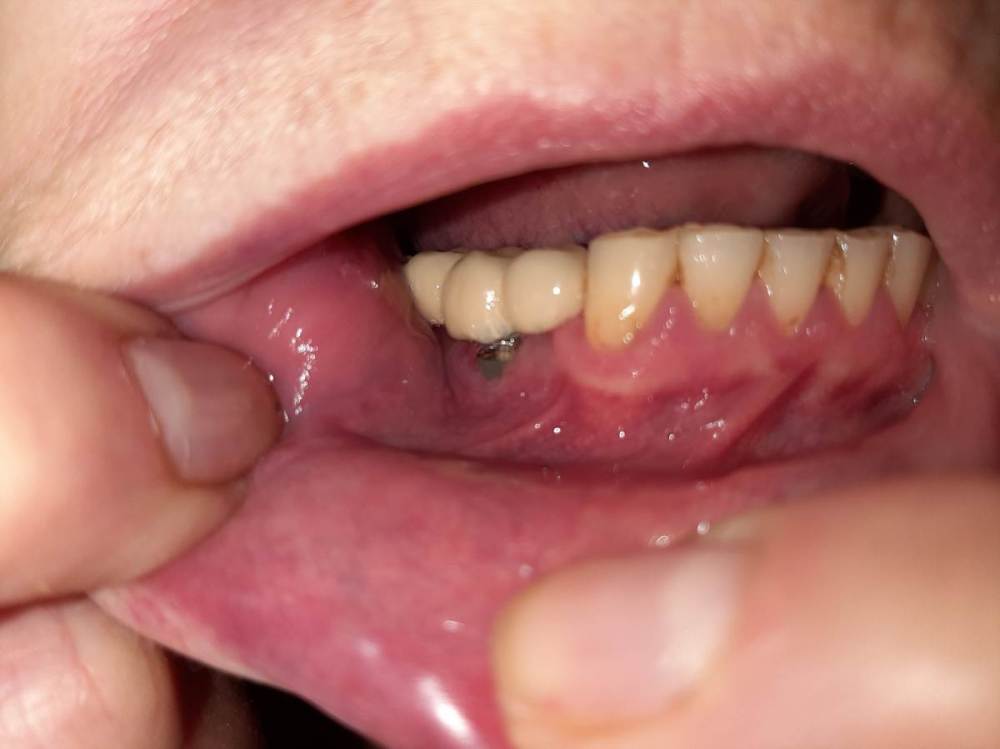

Вот с такой ситуацией обратилась к врачу, болел зуб мудрости.  Далее был сделан снимок (прилагаю фото решений- удаление опорных зубов с последующей заменой имплантами). PX20171201_162103_0000_000000FF.thumb.jpg.8c974cf49da3bb77db059abb91c7264c.jpg2018-01-24_013834.thumb.jpg.48a661d2a2f2d78a18d7b2906252d0a3.jpg2018-01-24_014845.thumb.jpg.0665ffa758959ace3ce9d7a8ff27421f.jpgпосле проведенных манипуляции появилась парастезия тройничного нерва, считаю это последствиями неверно установленного импланта, справедливо ли мое мнение?  Прохожу длительное лечение у невропатолога.  На крайнем визите врач отказал в помощи с этой проблемой и с обнаженным имплантом. (Прикладываю фото) 786267296_09_12_21.thumb.jpg.f332c30c240cb1ba19d2341b4f6014f1.jpg20220116_233530.thumb.jpg.c9cc82f18d25e9a905a2b7b1dc13eb8c.jpg20220116_232905.thumb.jpg.c3953c0b472c6e3ce1f46272ef507d2e.jpg1915694342_WhatsAppImage2022-08-20at19_39_20.thumb.jpeg.2099829af18d4d8c448126d5f323605f.jpegУ меня следующий вопрос:  верно ли назначенное лечение и насколько корректно установлены импланты, а также имелись ли противопоказания для установки имплантов, имея ввиду, что была убыль кости? Можно ли устанавливать импланты в таком случае?  прикладываю фото уже удаленного установленного на на импланты моста, правильно ли выполнен технически? (импланты пришлось удалить, а мост снять, чтобы сделать операцию по восстановлению кости, но уже в другой клинике. так как, как я писала выше, врач, установивший импланты отказал в помощи).